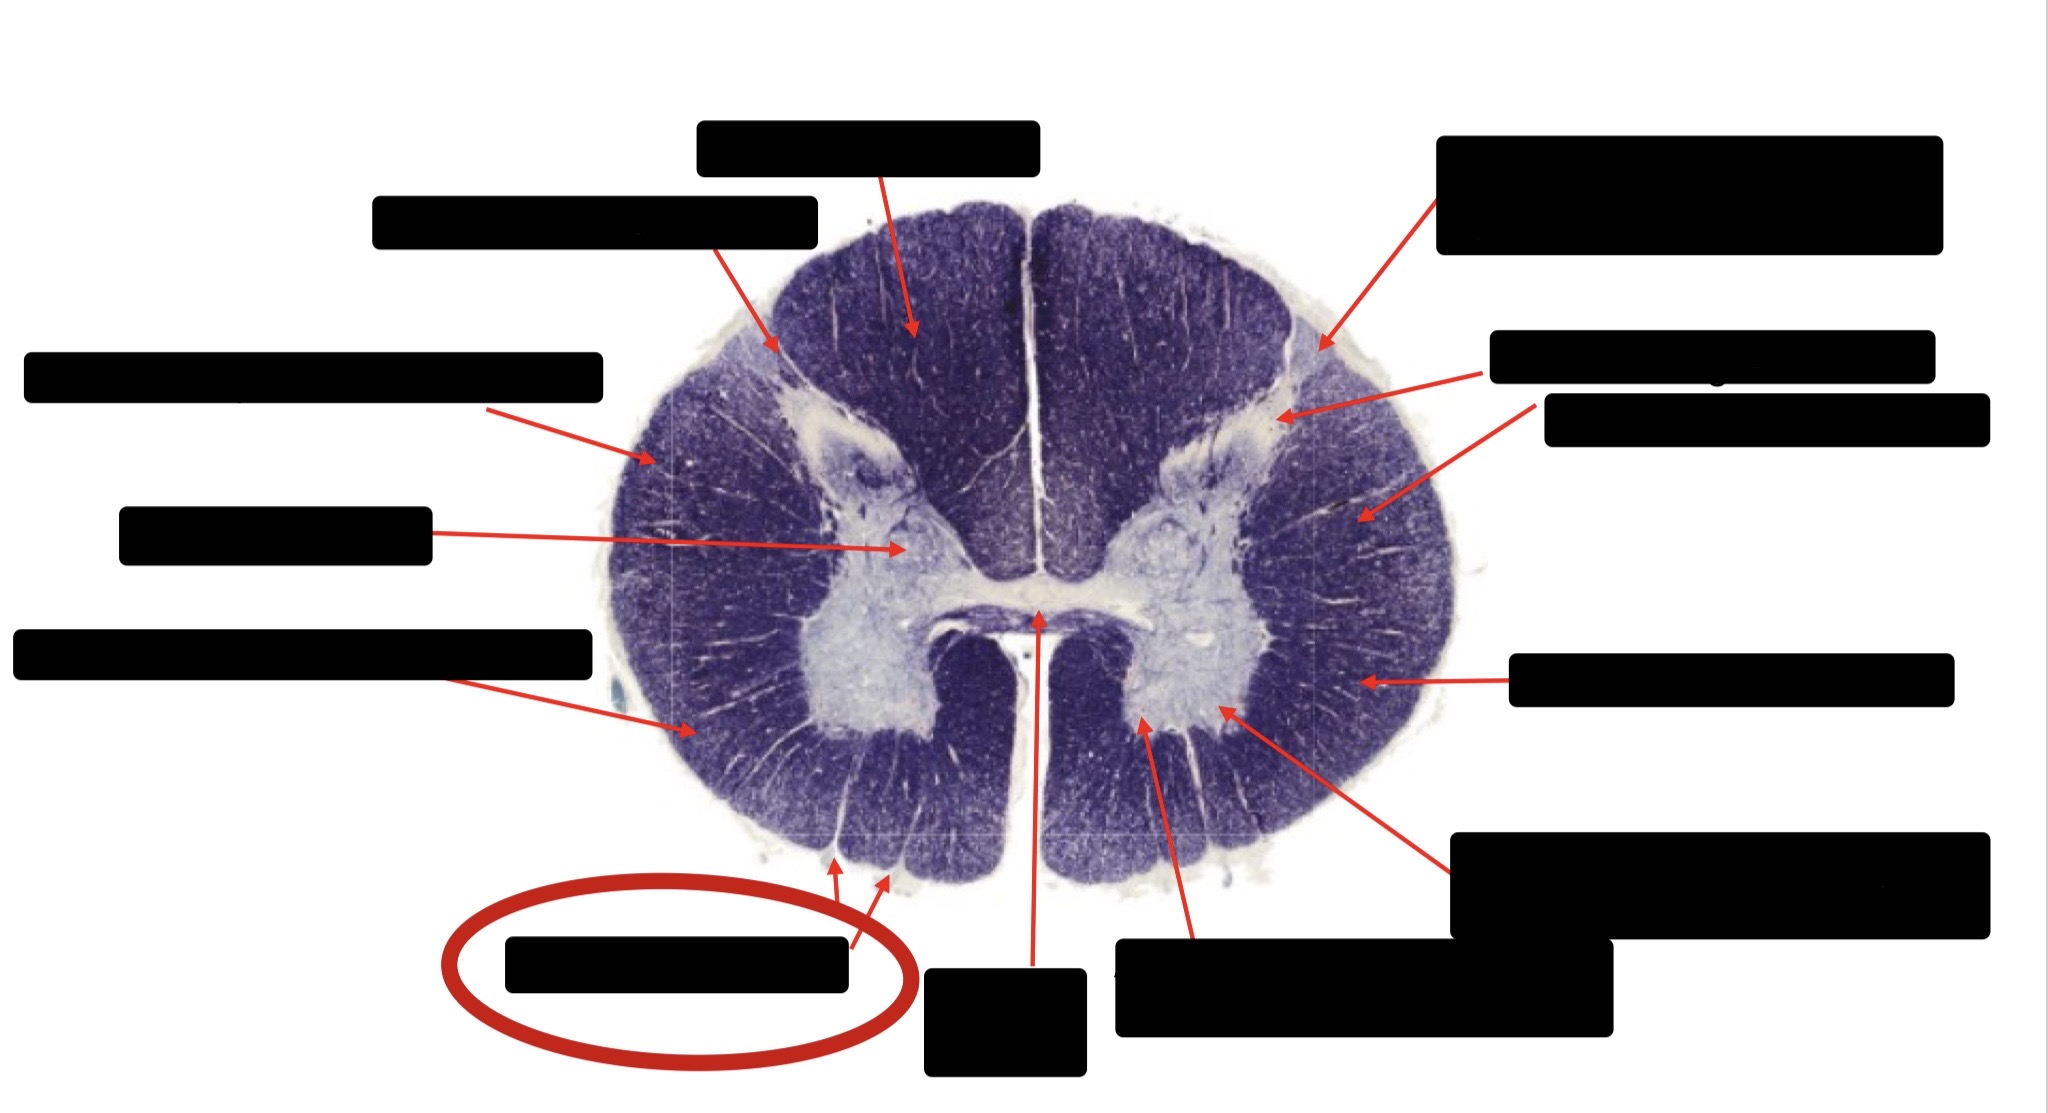

Anterior Spinal Artery

Denticulate Ligament

Ventral Root

Dorsal Root

Posterior Column Fasciculus Gracilis

Large Fiber Entry Zone

Central Canal

Dorsal Rootlet

Lissaeur’s Tract & Small Fiber Entry Zone

Substantia Gelatinosa

Lateral Corticospinal Tract

Anterior Horn Motor Neuron

Spinothalmic Tract

Anterior Horn Motor Neurons